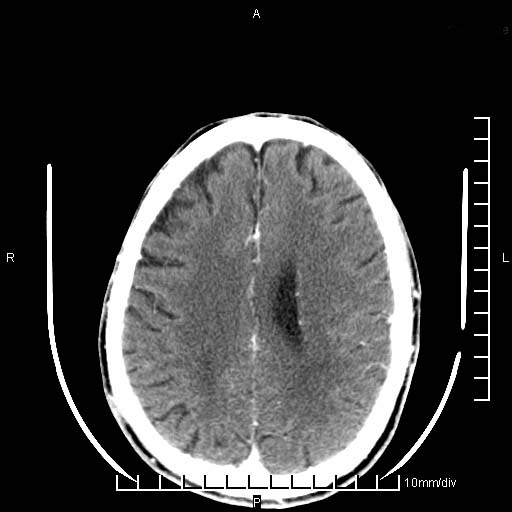

临床以双下肢浮肿,疼痛收治,无明显神经系统症状,既往无梗塞,出血病史。左颞叶见低密度灶,考虑什么?

考虑左侧颞叶脑软化灶。

无强化 无占位 软化灶吧

无强化、 无占位、局部脑沟增宽, 软化灶吧。